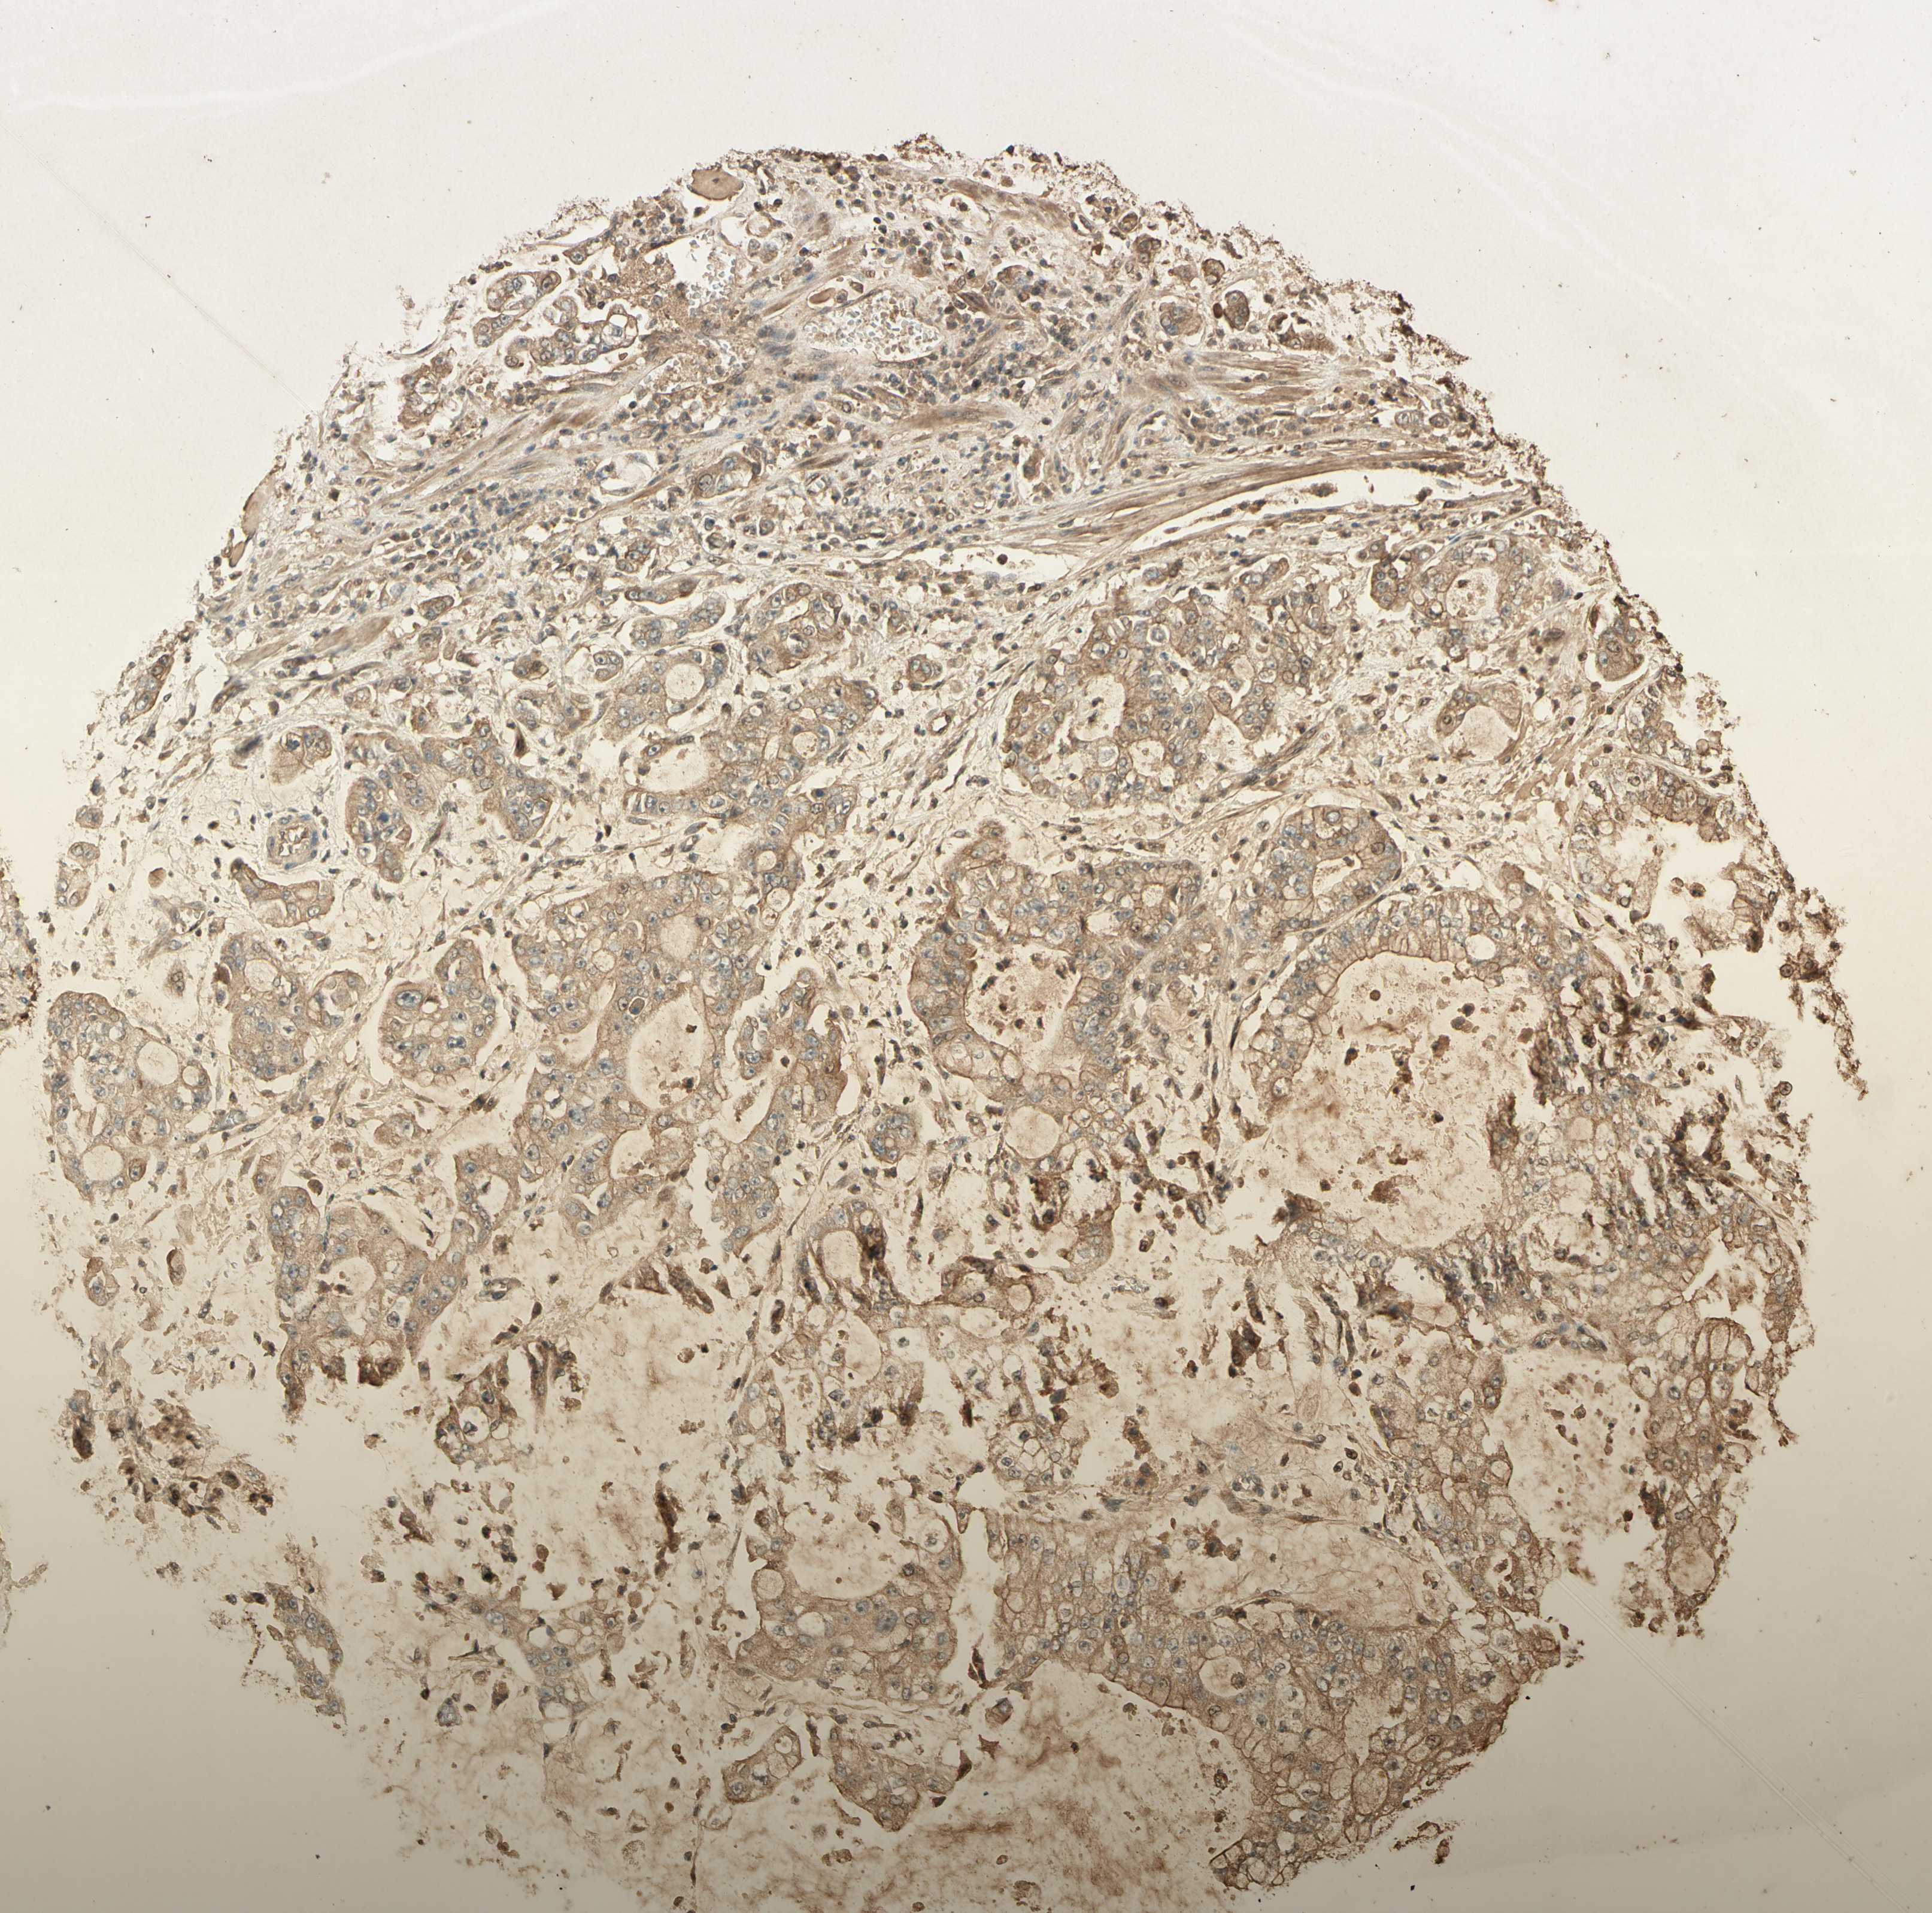

STOMACH CANCER - Protein expressioni

A mouse-over function shows sample information and annotation data. Click on an image to view it in a full screen mode. Samples can be filtered based on level of antibody staining by selecting one or several of the following categories: high, medium, low and not detected. The assay and annotation is described here.

Note that samples used for immunohistochemistry by the Human Protein Atlas do not correspond to samples in the TCGA dataset.

Antibody stainingi

Antibody staining in the annotated cell types in the current human tissue is reported as not detected, low, medium, or high, based on conventional immunohistochemistry profiling in selected tissues. This score is based on the combination of the staining intensity and fraction of stained cells.

Each image is clickable and will lead to virtual microscopy that enables deeper exploration of all samples and also displays staining intensity scores, fraction scores and subcellular localization as well as patient and tissue information for each sample.

Antibody HPA031162

Antibody CAB009119

Staining

High

Medium

Low

Not detected

Intensity

Strong

Moderate

Weak

Negative

Quantity

>75%

75%-25%

<25%

None

Location

Nuclear

Cytoplasmic/membranous

Cytoplasmic/membranous,nuclear

Adenocarcinoma, NOS

Adenocarcinoma, High grade